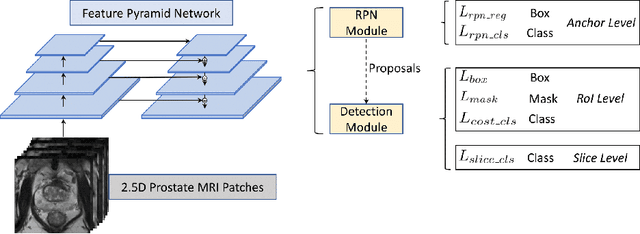

Prostate cancer (PCa) is one of the leading causes of death for men worldwide. Multi-parametric magnetic resonance (mpMR) imaging has emerged as a non-invasive diagnostic tool for detecting and localising prostate tumours by specialised radiologists. These radiological examinations, for example, for differentiating malignant lesions from benign prostatic hyperplasia in transition zones and for defining the boundaries of clinically significant cancer, remain challenging and highly skill-and-experience-dependent. We first investigate experimental results in developing object detection neural networks that are trained to predict the radiological assessment, using these high-variance labels. We further argue that such a computer-assisted diagnosis (CAD) system needs to have the ability to control the false-positive rate (FPR) or false-negative rate (FNR), in order to be usefully deployed in a clinical workflow, informing clinical decisions without further human intervention. This work proposes a novel PCa detection network that incorporates a lesion-level cost-sensitive loss and an additional slice-level loss based on a lesion-to-slice mapping function, to manage the lesion- and slice-level costs, respectively. Our experiments based on 290 clinical patients concludes that 1) The lesion-level FNR was effectively reduced from 0.19 to 0.10 and the lesion-level FPR was reduced from 1.03 to 0.66 by changing the lesion-level cost; 2) The slice-level FNR was reduced from 0.19 to 0.00 by taking into account the slice-level cost; (3) Both lesion-level and slice-level FNRs were reduced with lower FP/FPR by changing the lesion-level or slice-level costs, compared with post-training threshold adjustment using networks without the proposed cost-aware training.